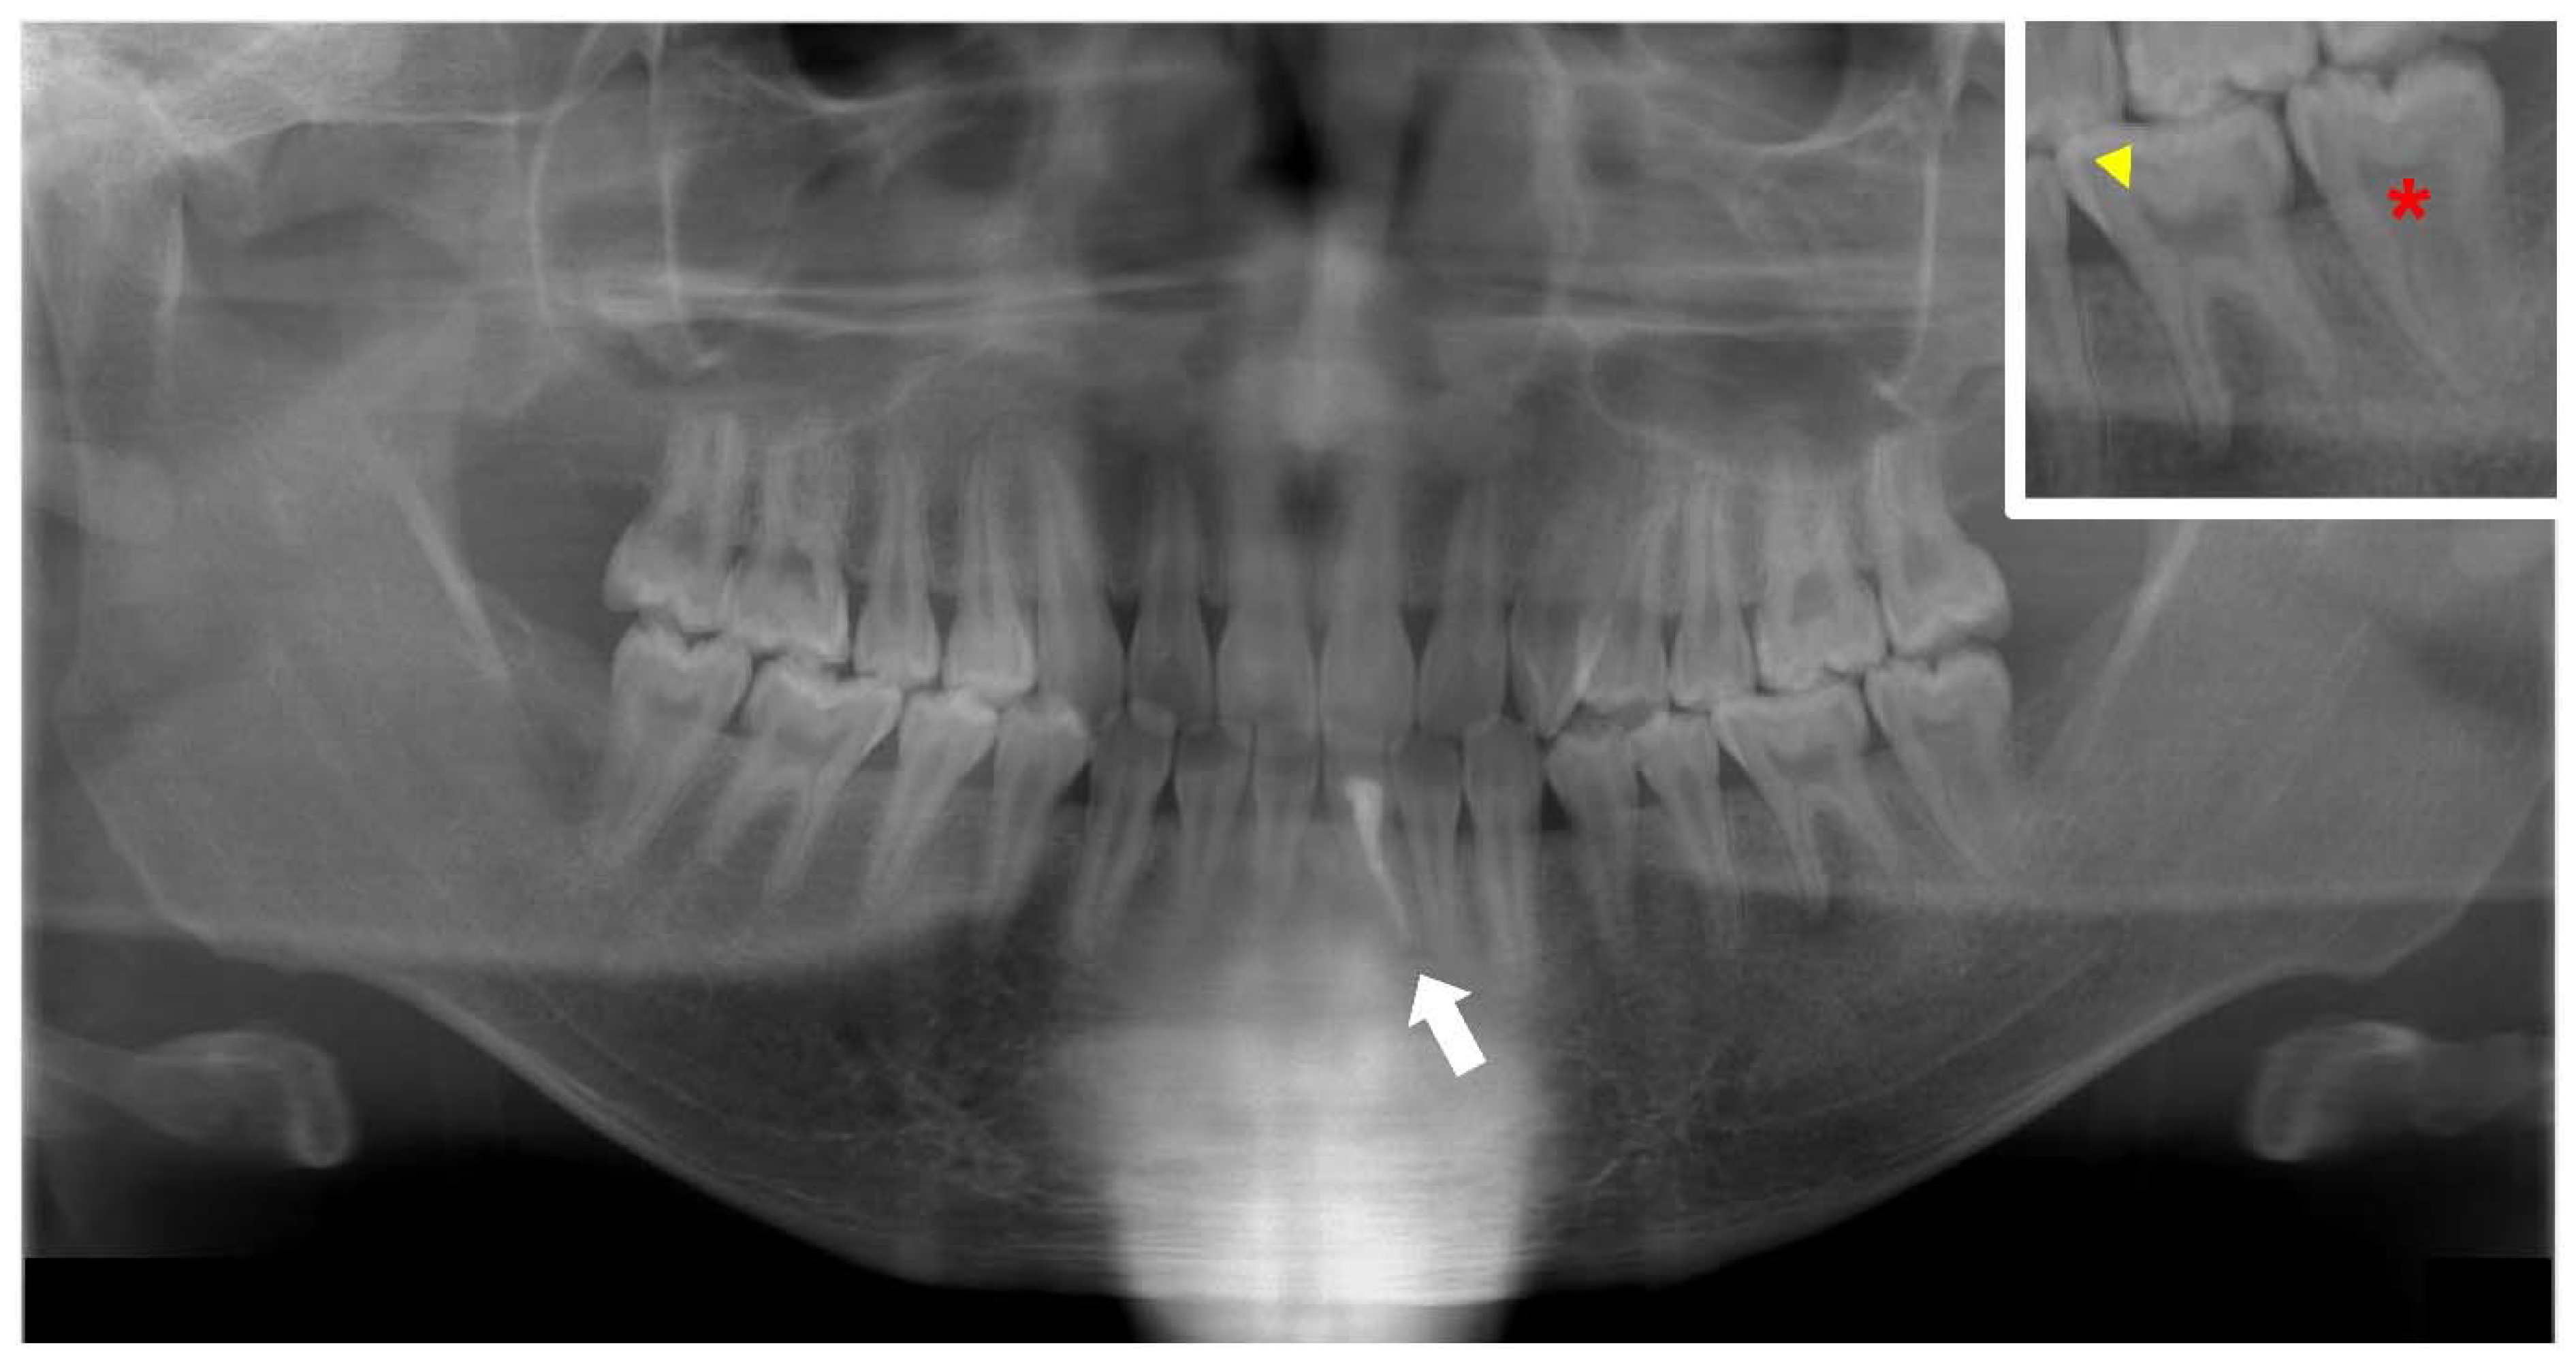

Endodontic infections due to poor dentin mineralization are also recognized in permanent teeth [40] (Figure 7). However, maxillofacial cellulitis is rare in adults with XLH [8]. Endodontically affected teeth are common in XLH patients, and the number of affected teeth increases significantly with age [41]. More than 60% of adults with XLH have experienced more than five dental abscesses [42]. The most commonly affected teeth are incisors and canines, followed by molars and premolars [41]. The order in which teeth are affected is determined not only by the time of eruption but also by the rate of natural attrition as a result of mastication [7]. High prevalence and severity of periodontitis are often recognized in adult patients with XLH [43]. Nearly 80% of adult XLH patients are reported to have moderate or severe periodontitis [44]. Periodontitis is a major cause of tooth loss in adults with XLH [8].

Figure 7.

Panoramic radiograph of the permanent dentition of a male X-linked hypophosphatemia (XLH) patient aged 21 years who underwent root canal treatment of the mandibular left central incisor associated with a cystic swelling (arrow). The square on the upper right is an enlargement of the primary mandibular left molar region. Wide pulp chambers (asterisks) and prominent pulp horns (arrowheads) can be seen.